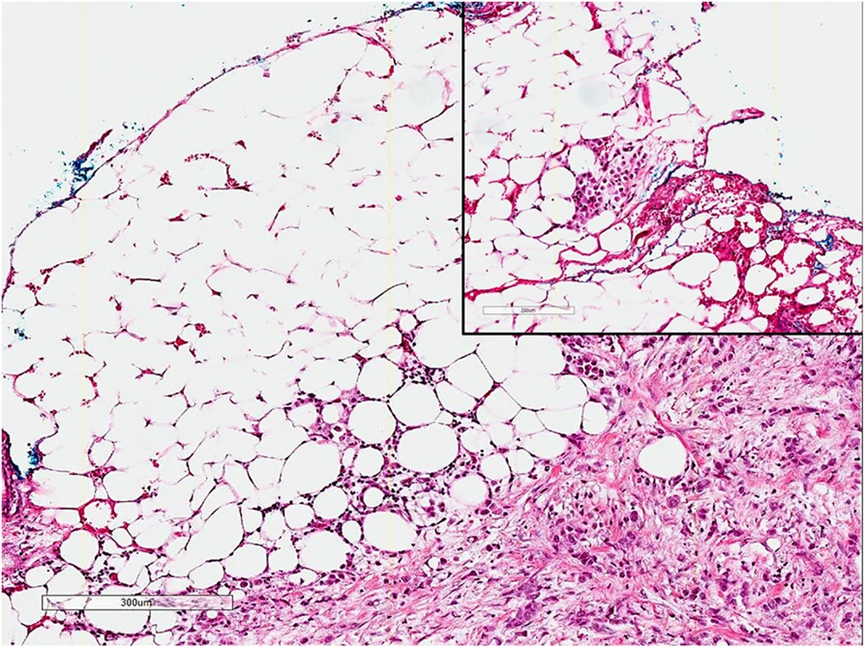

图4A. PUC对膀胱壁的弥漫性浸润;图4B显示血管内瘤栓

图5. PUC沿着脂肪组织浸润生长至手术切缘

PUC中大约有一半是纯粹的浆细胞样尿路上皮癌,但也可以伴发于经典的尿路上皮癌、肉瘤样尿路上皮癌、微乳头状尿路上皮癌,巢状尿路上皮癌和小细胞癌。细胞排列成条索状,列兵样,小巢状,实性成片,偶尔会呈现欺骗性的良性外观,从而误诊为炎症。间质可能呈黏液样外观,并可见胞质内空泡,但并不是真正的印戒细胞。在30%–43%的病例中存在血管浸润。在现在报道的病例中,肿瘤分期为pT3或更高的PUC占56%~100%,淋巴结转移为20%~73%。PUC呈弥漫性浸润生长模式,可沿骨盆筋膜平面局部播散,累及骨膜、直肠周围和输尿管周围软组织,腹膜播散发生在33%至68%患者。